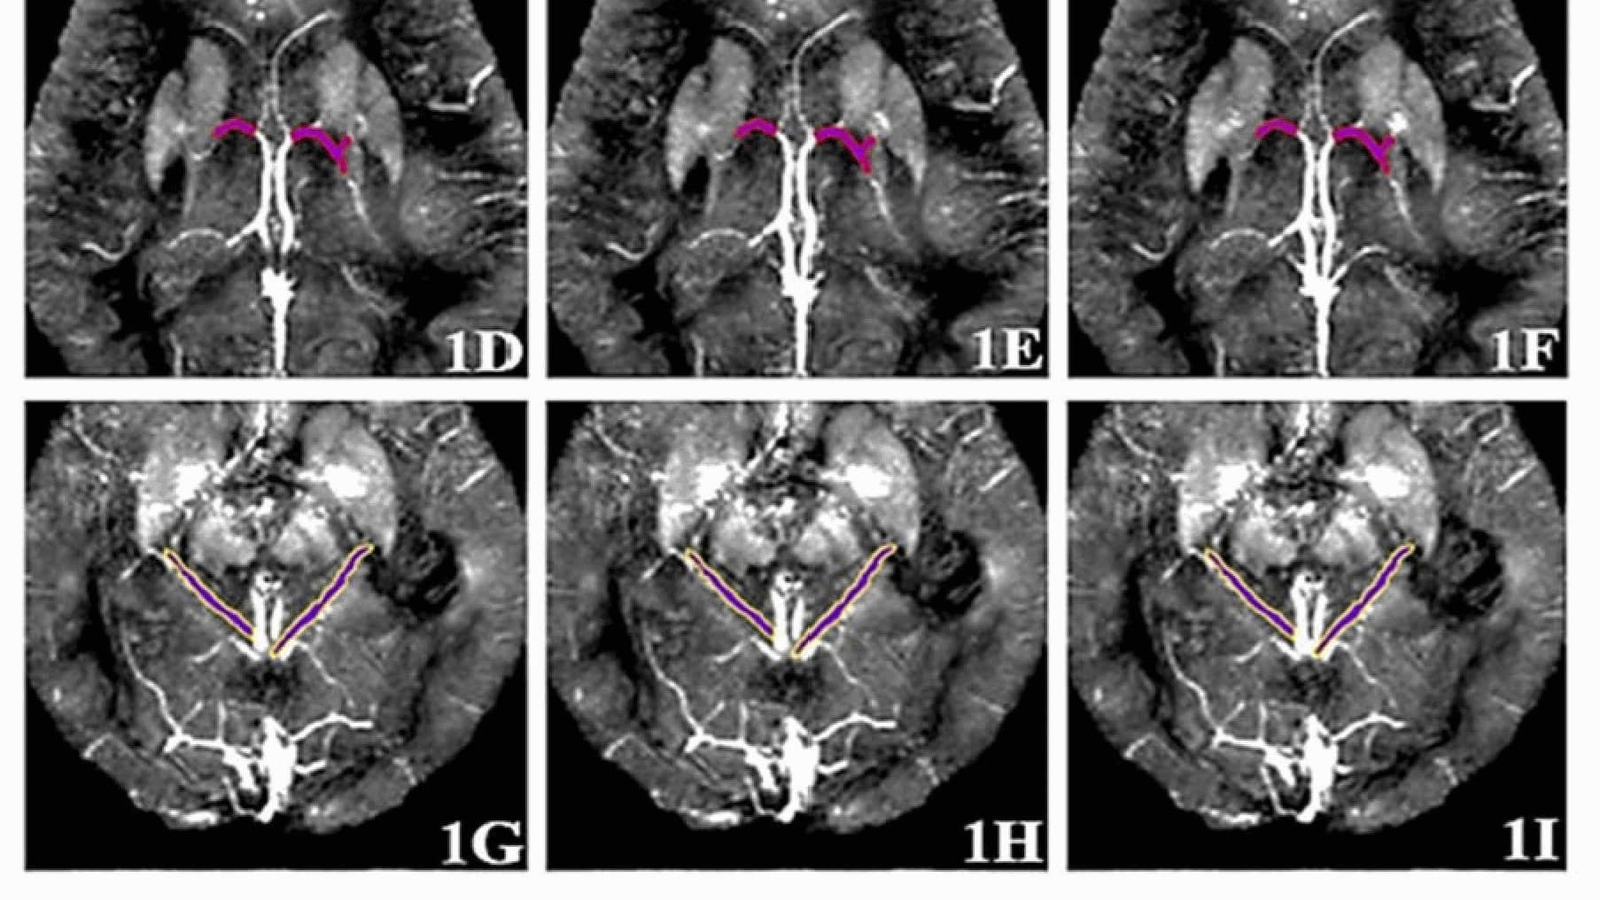

Томографические снимки вен головного мозга

Метод основан на анализе магнитной восприимчивости шести вен головного мозга с помощью МРТ с контрастным усилением. Полученные данные обрабатываются алгоритмом машинного обучения — «деревом решений», которое классифицирует состояние пациента как здоровое (CON) или указывающее на болезнь Альцгеймера (AD).

На практике это выглядит следующим образом. Пациенту вводят контрастное вещество на основе гадолиния, которое усиливает сигнал МРТ, где человек проходит сканирование головного мозга. Далее специалисты измеряют магнитную восприимчивость в шести мозговых венах. Эти параметры дают важную информацию о состоянии кровеносных сосудов и уровнях кислорода, которые могут меняться при развитии болезни Альцгеймера.